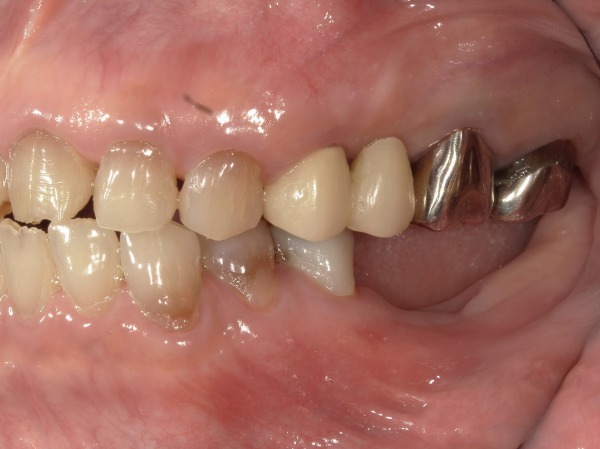

患者様は60代の女性の方です。当院にメンテナンスで通院しておられましたが、他院にて入れた左下の被せ物が虫歯で取れてしまいました。虫歯をしっかり削っていくと、ご自身の歯がほとんどなくなってしまい、被せ物を再度行うことが不可能となり、残念ながら抜歯となりました。

抜歯後のお口の状態がこちらになります。

適合が問題ないことや歯茎とぶつかっている部位がないことなど念入りに確認し、噛み合わせも細かく調整を行いセットいたしました。毎日ご自身で着脱を行なってもらいますので、着脱の練習も十分にしてもらいました。